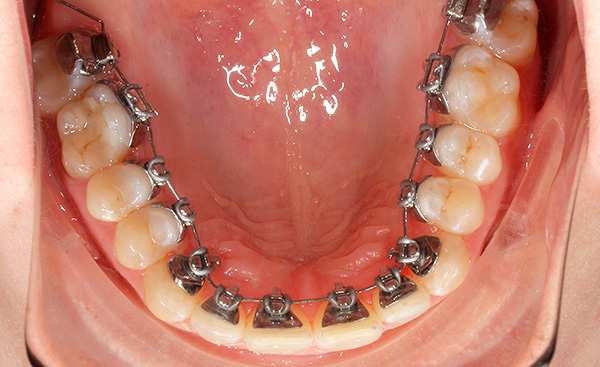

La prima opzione: sistemi di staffe linguali - l'ortodontista li attacca ai denti dal palato e dalla lingua, e quindi le persone intorno non sospettano che la persona indossi le parentesi graffe.

Esistono due varietà di tali sistemi: apparecchi linguali standard, i cosiddetti sistemi 2D. Sono prodotti dalla fabbrica, hanno forma e dimensioni standard, sono in grado di spostare i denti in uno spazio bidimensionale. Il medico lega l'arco che sposta i denti alle serrature con legature di metallo o di gomma.

La capacità di muovere i denti utilizzando tali sistemi è limitata a causa della loro forma convessa standard e dell'adattamento incompleto dell'arco attivo. Come dicono molti ortodontisti che usano queste parentesi graffe, è difficile ottenere un morso ideale nel trattamento di patologie ortodontiche complesse, poiché l'effetto è principalmente sulla corona del dente e la posizione delle radici rimane praticamente invariata.

La seconda opzione: apparecchi ortodontici 3D individuali - sono realizzati in lega d'oro in laboratorio singolarmente per ciascun paziente, tenendo conto della forma di ciascun dente e della sua inclinazione. Insieme alle parentesi graffe, il medico ordina una serie di archi attivi per l'intero periodo di correzione dell'occlusione. Questo approccio offre una perfetta aderenza ai denti e la possibilità di regolare la loro posizione insieme alle radici.